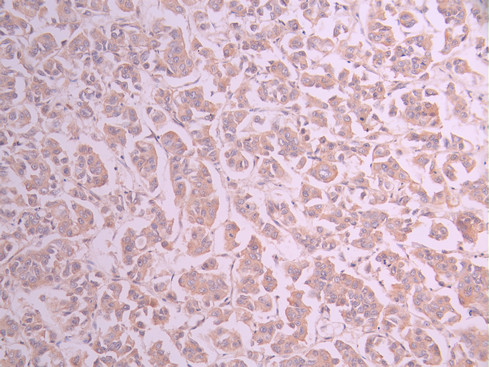

IHC image of CSB-RA183712A0HU diluted at 1:100 and staining in paraffin-embedded human breast cancer performed on a Leica BondTM system. After dewaxing and hydration, antigen retrieval was mediated by high pressure in a citrate buffer (pH 6.0). Section was blocked with 10% normal goat serum 30min at RT. Then primary antibody (1% BSA) was incubated at 4°C overnight. The primary is detected by a Goat anti-rabbit polymer IgG labeled by HRP and visualized using 0.05% DAB.